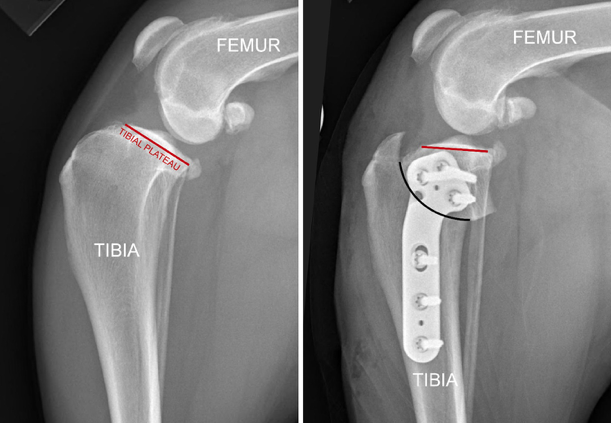

We have already discussed above how the tibial plateau is sloped downhill and backwards by about 30 degrees in the average dog. In order to prevent the femur from sliding off the back of the tibia we level the top of the tibia. We do this by making a semi-circular cut in the top of the tibia and rotating that portion of the tibia until the plateau is now leveled. We then have to secure the tibia with a bone plate and screws (similar to how we treat a fracture). The femur then sits back on top of the tibia instead of sliding off the back of the tibia. Please see the next images.

The image above shows a tibial plateau that is sloped backwards at about 30 degrees and the femur has slid off the back. A semi-circular cut (ie osteotomy) is made in the tibia and is shown by a black line in the image on the R. The top segment is rotated until the tibial plateau is now between 0-5 degrees (as shown on the right). A bone plate with 6 screws is then applied to hold the tibia in this position. Now the femur sits back on top of the tibia again as is shown in the image on the right.